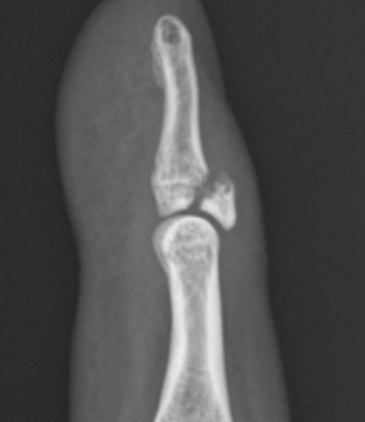

指の骨折

指の骨折です。突き指を間違いやすいので、医療機関をご紹介いたしました。

早くスポーツ復帰ができると良いですね。